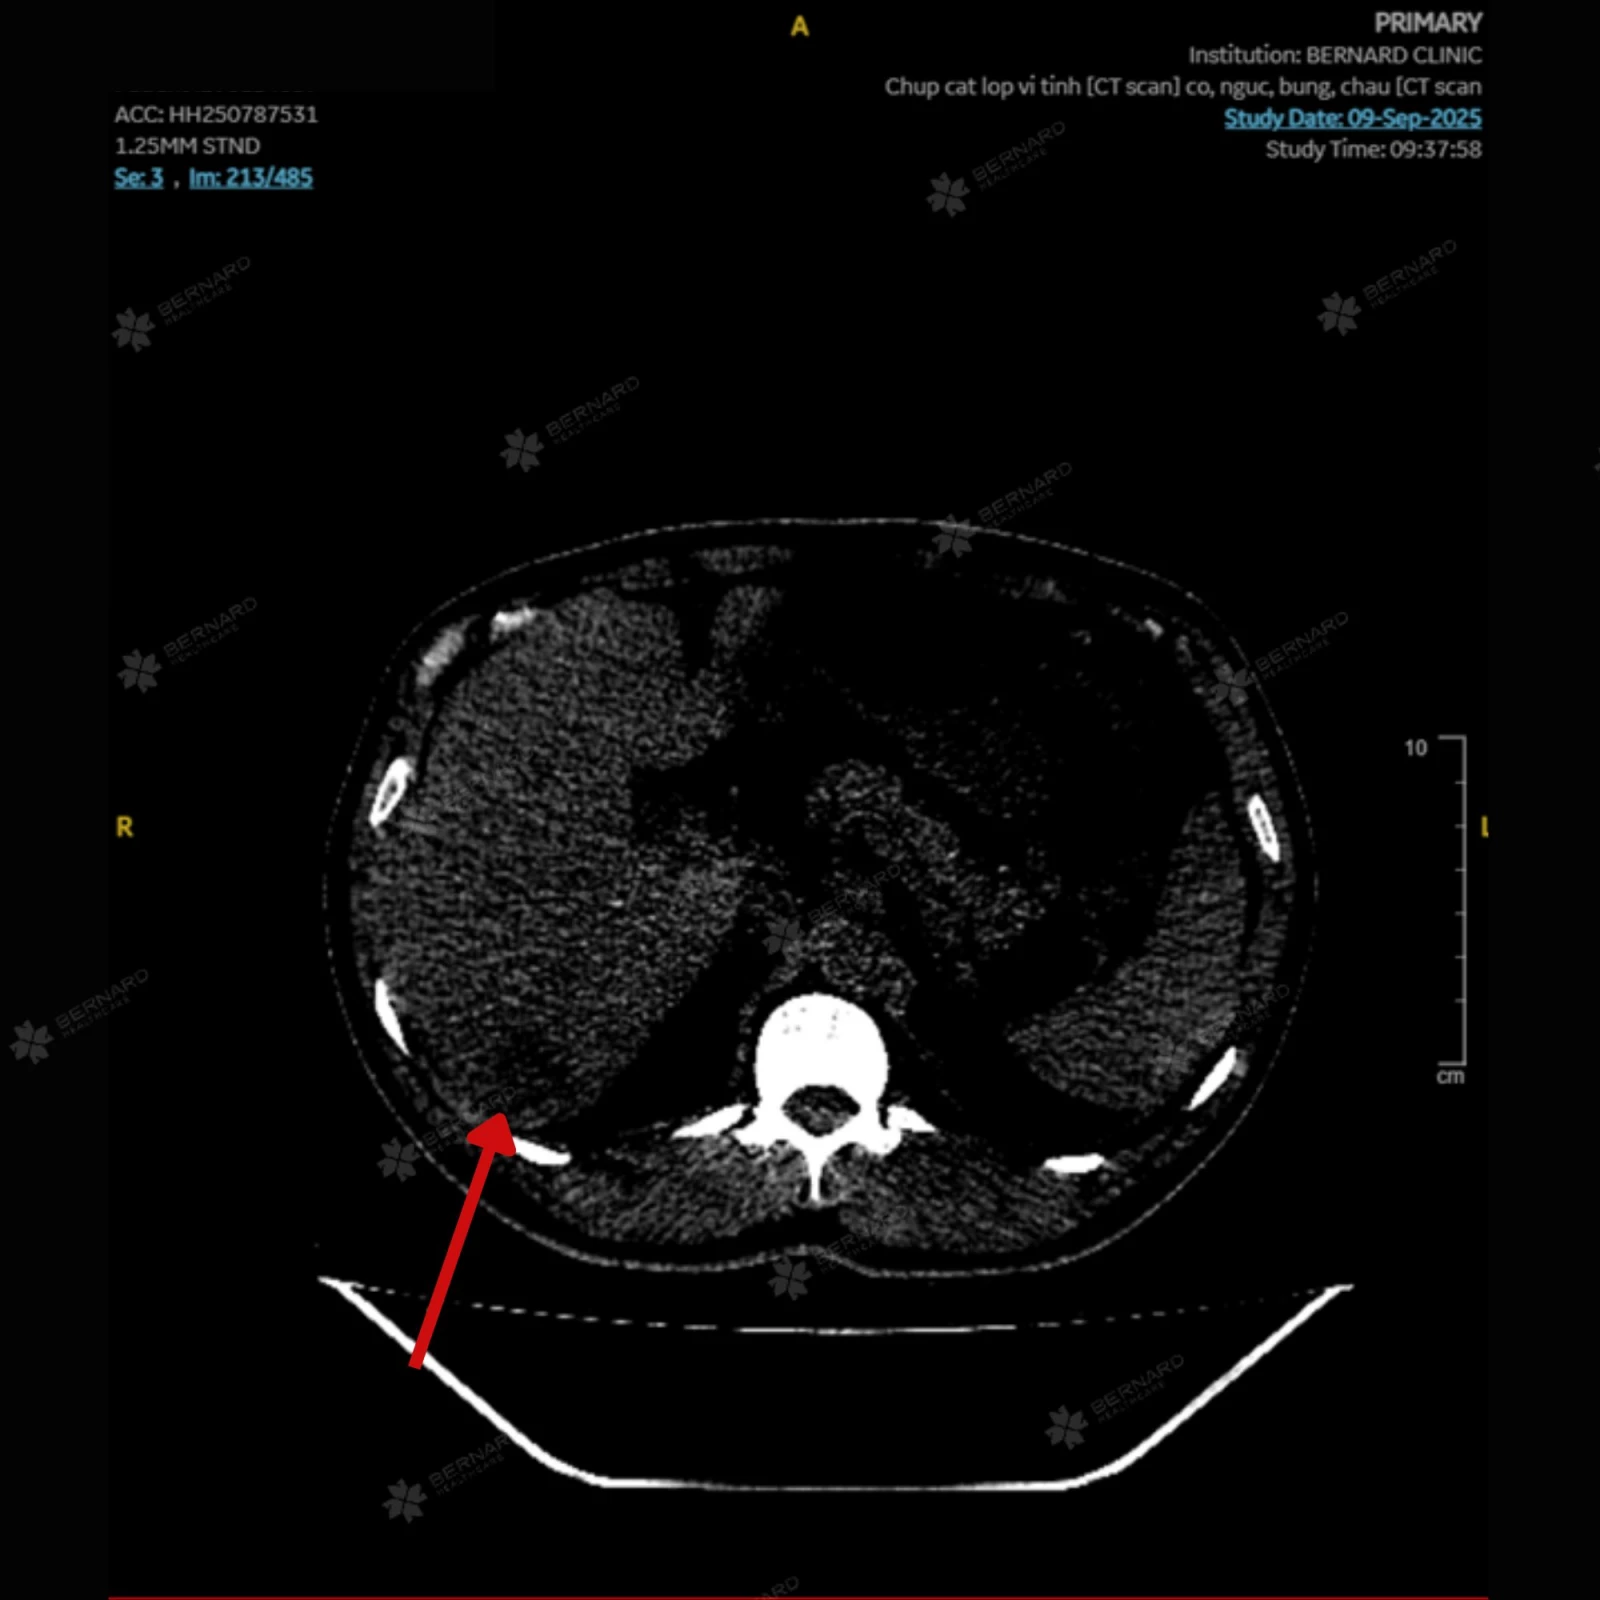

Qua chẩn đoán hình ảnh ban đầu, bác sĩ Bernard ghi nhận gan anh H. không to, bờ đều, tuy nhiên có một ổ dạng nang nhỏ khoảng 6mm tại phân thùy VI. Đáng chú ý hơn, ở ranh giới phân thùy này xuất hiện một vùng đậm độ thấp, đường kính khoảng 3cm với bờ không rõ, khiến bác sĩ Bernard nghĩ nhiều đến một tổn thương tiềm ẩn.

Do đặc điểm tổn thương có thể chồng lấp giữa các bệnh lý lành tính và ác tính, hình ảnh CT Scan được gửi đến Bệnh viện Đại học Yamanashi (Nhật Bản) để tham vấn ý kiến thứ hai.

Tại đây, các bác sĩ Nhật cũng ghi nhận một vùng giảm đậm độ khoảng 35mm ở phân thùy S6, nghi ngờ u máu hoặc thâm nhiễm mỡ khu trú, song chưa thể loại trừ hoàn toàn nguy cơ ác tính. Đồng thời khuyến nghị làm thêm các cận lâm sàng chuyên sâu.